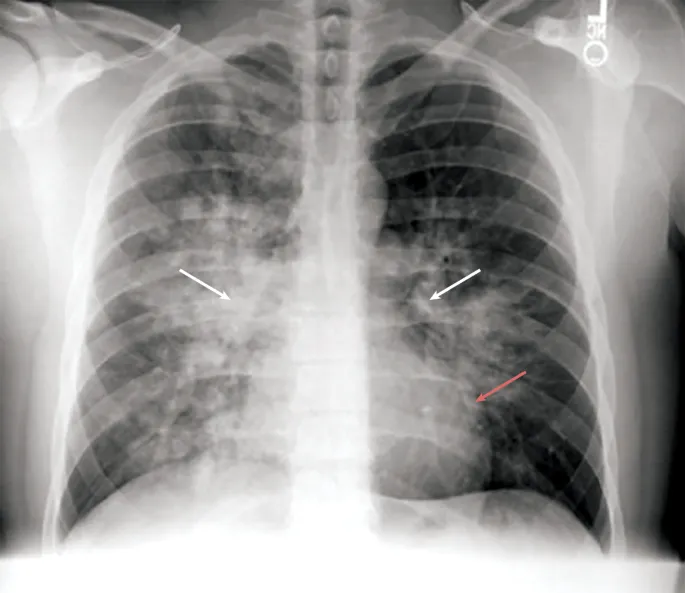

| Key Symptoms | Severe headache, nausea/vomiting, profound lethargy → ataxia, confusion, altered consciousness, coma. | Dyspnea at rest, persistent cough (frothy/pink sputum), chest tightness, extreme fatigue. |

| Key Signs | Ataxia (critical!), papilledema, retinal hemorrhages, ↓consciousness. 📌 "Can't Walk, Can't Talk" | Tachypnea, tachycardia, cyanosis, rales/crackles on auscultation. 📌 "Can't Breathe, Frothy Wreath" |

| Pathophysiology | Vasogenic/cytotoxic cerebral edema due to hypoxia. | Uneven hypoxic pulmonary vasoconstriction → ↑pulmonary artery pressure → capillary leakage. |

| Primary Treatment | Immediate Descent, Oxygen, Dexamethasone (8mg stat, then 4mg 6-hourly) | Immediate Descent, Oxygen, Nifedipine (30mg SR BD or 10mg stat then 20mg SR), CPAP/PEEP |